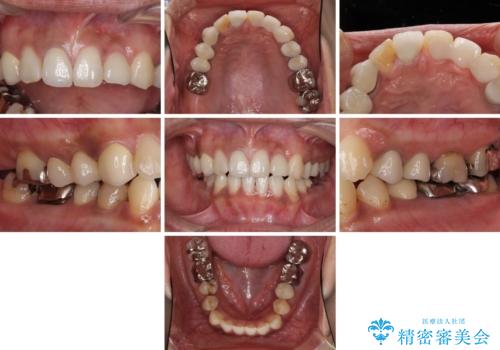

- 歯を削る量が少ないとの触れ込みで最近接着ブリッジを装着したものの、そのブリッジと歯の間に隙間ができているとのことで来院された患者様です。

歯の裏側を一層だけ削り、接着力に頼ったブリッジを装着してはみたものの、案の定咬む力に負けて、接着が剥がれてしまっていました。

歯を削る量は増えますが、より長い期間再治療なく使用していただくことを最優先に考え、フルカバレッジのオールセラミックブリッジにて補綴することとしました。

他にも、奥歯の銀歯の下にもむし歯が多くあり、痛みが生じていたため、根管治療などを行った上で、オールセラミッククラウンにて補綴治療することとしました。

前歯の裏側の接着面は、隙間ができていたことにより、汚れがたまるだけでなく、むし歯にもなっていました。

我々としては、治療により状態が悪化することだけは避けたいと考えているため、歯全体を覆うクラウンにすることで、より長持ちする治療を提供いたしました。

外観はもちろんのこと、隙間なく安心して咬むことのできる前歯となり、患者様には大変満足していただきました。